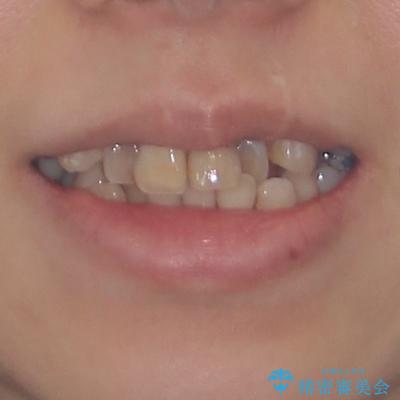

気になる八重歯と変色した前歯 抜歯矯正とセラミッククラウン治療

- 前歯の八重歯やデコボコを気にして来院された患者様です。

口元の突出感はありませんが、前歯の重なりが著しいため、目立ちにくい表側のワイヤー装置にて、上下左右の第一小臼歯4本を抜歯して矯正治療を行うこととしました。

上顎前歯4本は、以前むし歯により神経をすべて取り除かれており、その影響で既に変色を起こしている状態でした。

4本とも歯根部先端の骨が炎症により吸収していることがレントゲン写真から示唆されたため、矯正治療後に4本を再根管治療し、その後上顎6歯をオールセラミッククラウンにて補綴治療することとしました。